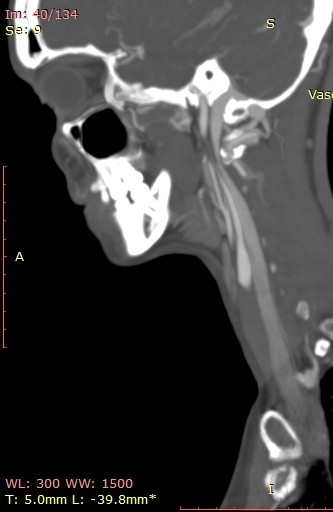

So my daughter had her icp monitoring done two days ago. They kept her at Hopkins until this evening and the results have not been officially given although they said that the fluctuations in her head pressure were not enough to consider it a problem with her csf so that is a good thing. Her pressure did rise significantly whenever she bent over or when her head went below her heart. Now we are left with the real possibility that the pressure has been coming from her jugular vein compression all along. We have a telecall with Dr. Costantino in early March so hopefully he will be able to look at her imaging and confirm that she does have compression at the C1 level. I’m not sure that her styloids are part of the equation but I think it is clear from the imaging that the C1 is involved. I’m going to upload many of her images that I was able to make into 3d with RadiAnt but I’m not sure how good they are. I would appreciate anyone who can view them to give me their opinion on anything they may see that could be causing her head pressure. I did include some 2D images as well because they do seem to show the C1 compression of the jugular.

I’ve annotated a couple of the images you posted & will explain what I see under each image.

On the left side, your daughter’s IJV looks compressed at the styloid/skullbase level, possibly at C1 then lower between C4-C6. Because her cervical spine is so straight, it almost appears the transverse processes of those 3 vertebrae are in contact with her IJV & even below them. She has quite a number of collateral veins in the area of her skull base which is an indication of IJV compression. Though I can’t see the very tip of the greater horn of her hyoid bone on this side, it almost looks like it could be in contact with her external carotid artery (ECA) which can cause different symptoms than the IJVs.

There are very similar situations with the right side though I can’t see enough of the hyoid bone on this side to comment about the right greater horn.

Her compression doesn’t look severe, but since she’s symptomatic, the compression is enough for her body to be reacting to it. That Hopkins confirmed its not high enough to be a problem is good & bad. Good because she’s at lower risk for a CSF leak, but bad because I feel, in some respect, they were saying IH isn’t causing her symptoms which it most likely is.

Her styloids are very wide at the skull base & are not very well defined. I think that’s why her IJVs looked compressed to me right at the styloid/skull base junction, but you’ll need to see what Dr. Costantino thinks.